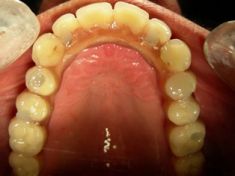

Paziente con problemi parodontali. Sono stati estratti i denti residui in arcata, inseriti gli impianti e, dopo poche ore, inserita la protesi

Paziente con problemi parodontali. Implantologia a carico immediato

Implantologia post estrattiva a carico immediato